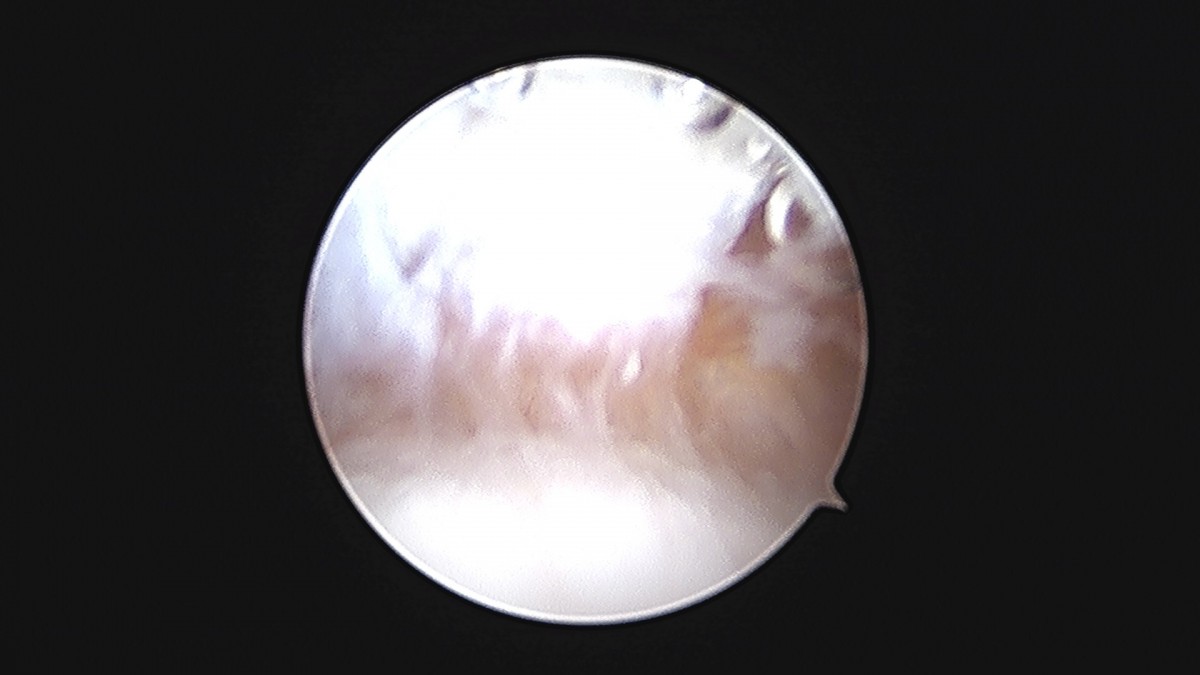

이재상원장님 발목 연골병변 제거술 및 골수 자극술 장경O 환자

작성자 최고관리자 댓글 0건 조회 375회 작성일 25-09-16 16:14